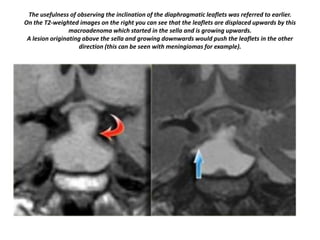

The usefulness of observing the inclination of the diaphragmatic leaflets was referred to earlier.

On the T2-weighted images on the right you can see that the leaflets are displaced upwards by this

macroadenoma which started in the sella and is growing upwards.

A lesion originating above the sella and growing downwards would push the leaflets in the other

direction (this can be seen with meningiomas for example).

The usefulness ofobserving the inclination of the diaphragmatic leaflets was referred to earlier. On the T2-weighted images on the right you can see that the leaflets are displaced upwards by this macroadenoma which started in the sella and is growing upwards. A lesion originating above the sella and growing downwards would push the leaflets in the other direction (this can be seen with meningiomas for example).